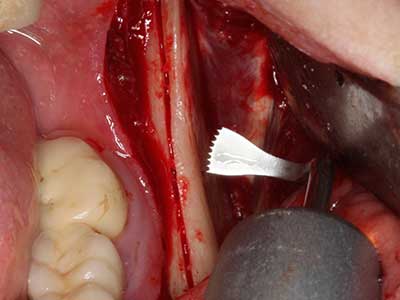

En la extracción de bloques óseos la piezocirugía también presenta ventajas adicionales: Además de la alta precisión en la osteotomía que ya se ha descrito antes, se ha comprobado que el uso de los delgados insertos de sierra resulta especialmente cuidadosas con el hueso. Frente a esto, sobre todo cuando se usan las fresas de Lindemann, cabe esperar pérdidas en la extracción significativamente más altas debido al mayor grosor de la parte frontal del cabezal (Lakshmiganthan, Gokulanathan et al. 2012). La separación basal que se necesita en particular en los injertos de bloque extraídos de forma retromolar se ve facilitada mediante sierras perpendiculares especialmente previstas a tal fin, lo que permite considerar que la cirugía piezoeléctrica es un procedimiento preciso y seguro para la obtención de bloques de hueso en el área retromolar (Happe 2007) (fig. 1-12).

Fig. 3: La separación basal del bloque se ve facilitada con piezas dotadas de una angulación especial.

Fig. 4: Con la rasqueta ósea se obtienen virutas adicionales de hueso autógeno.